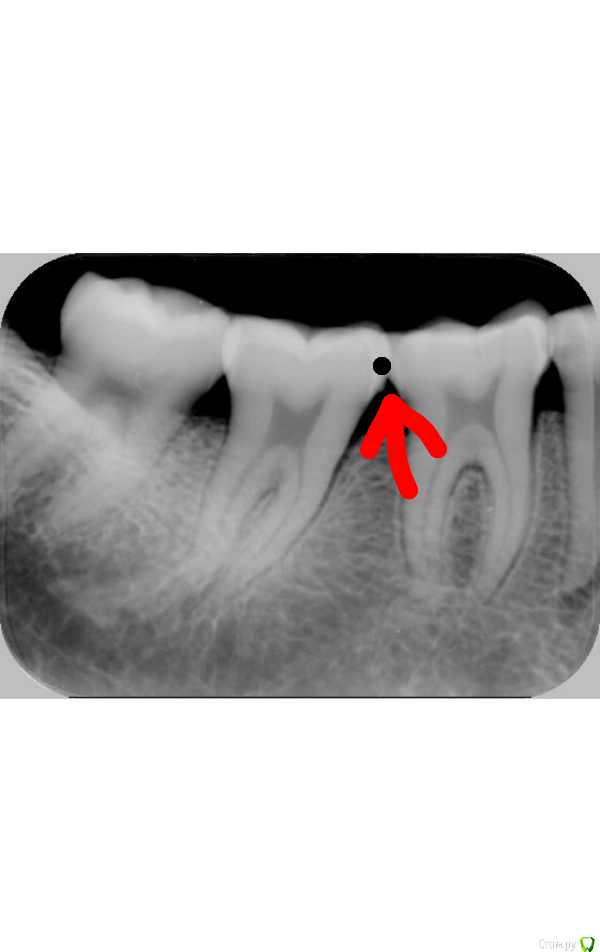

user7887 Опубликовано 24 июня, 2018 Автор Поделиться Опубликовано 24 июня, 2018 Расположение как на первом снимке,выглядит как на фиссуре на фото. 1 1 Ссылка на комментарий

user7887 Опубликовано 24 июня, 2018 Автор Поделиться Опубликовано 24 июня, 2018 (изменено) Покажите свои снимкиВот рентген снимок,фото к сожалению нету,до этого не фоткал,а теперь проблемное место между зубов( Изменено 24 июня, 2018 пользователем user7887 Ссылка на комментарий

user7887 Опубликовано 24 июня, 2018 Автор Поделиться Опубликовано 24 июня, 2018 Снимок в качестве Ссылка на комментарий